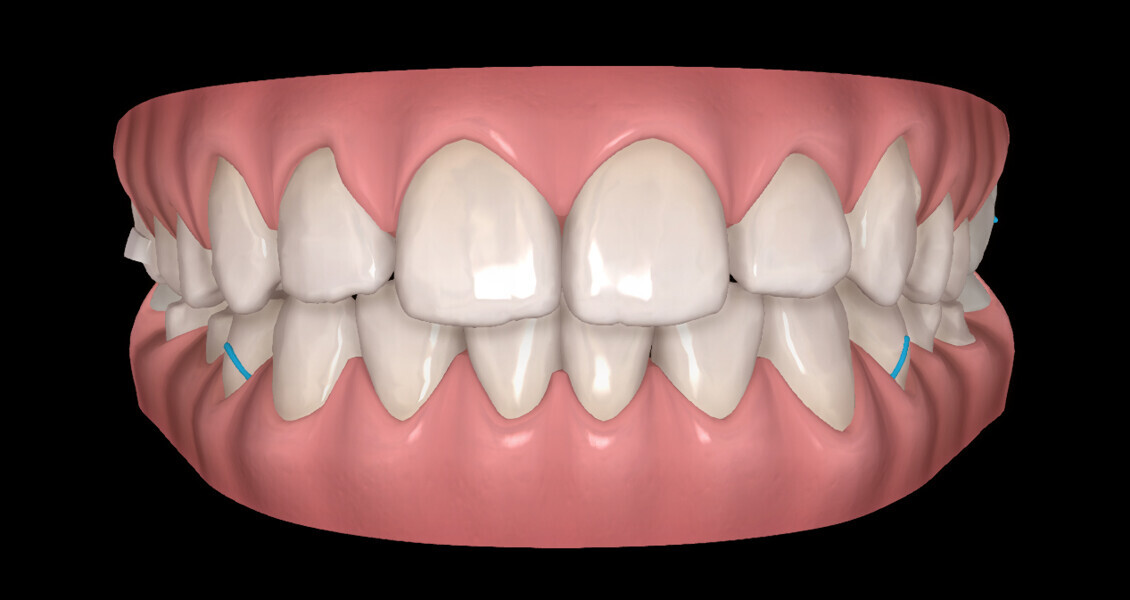

The digital treatment plan (ClinCheck) provided 18 aligners in each arch. The treatment objectives were focused on aligning and levelling the mandibular arch without excessively proclining the mandibular incisors, in order to control the Class III skeletal malocclusion by means of interproximal reduction and slicing of tooth #85. In the maxillary arch, the treatment plan focused on space creation for tooth #13 by distal rotation of the maxillary right molar and mesialisation of the maxillary right lateral incisor simultaneously to centre the midlines. Class II elastics were planned to control distal movement on the right side, and triangular elastics on the high canine were planned on the left side with button cutouts for the aligners. Lateral and posterior maxillary torque were planned to be close to 0° to achieve wider arch design and ideal intercuspation. No digital over-engineering was planned in the set-up, and lingual attachments according to personal preference were placed in the maxillary arch for aesthetic and biomechanical reasons (Figs. 15–19). Eruption compensation for tooth #13 was employed. Because of the age of the patient, the aligners were changed every seven days over the treatment period of less than five months.

At the end of the first stage of aligner treatment (Figs. 20–24), the auxiliary phase began with the bonding of two MTAs on the maxillary right premolars. A 0.016-in Australian archwire, shaped into a cantilever configuration, was then inserted into the MTAs, and a cutout was created on the final aligner. To prevent rotation, the archwire was cinched distal to tooth #15 and the cinch covered with composite.